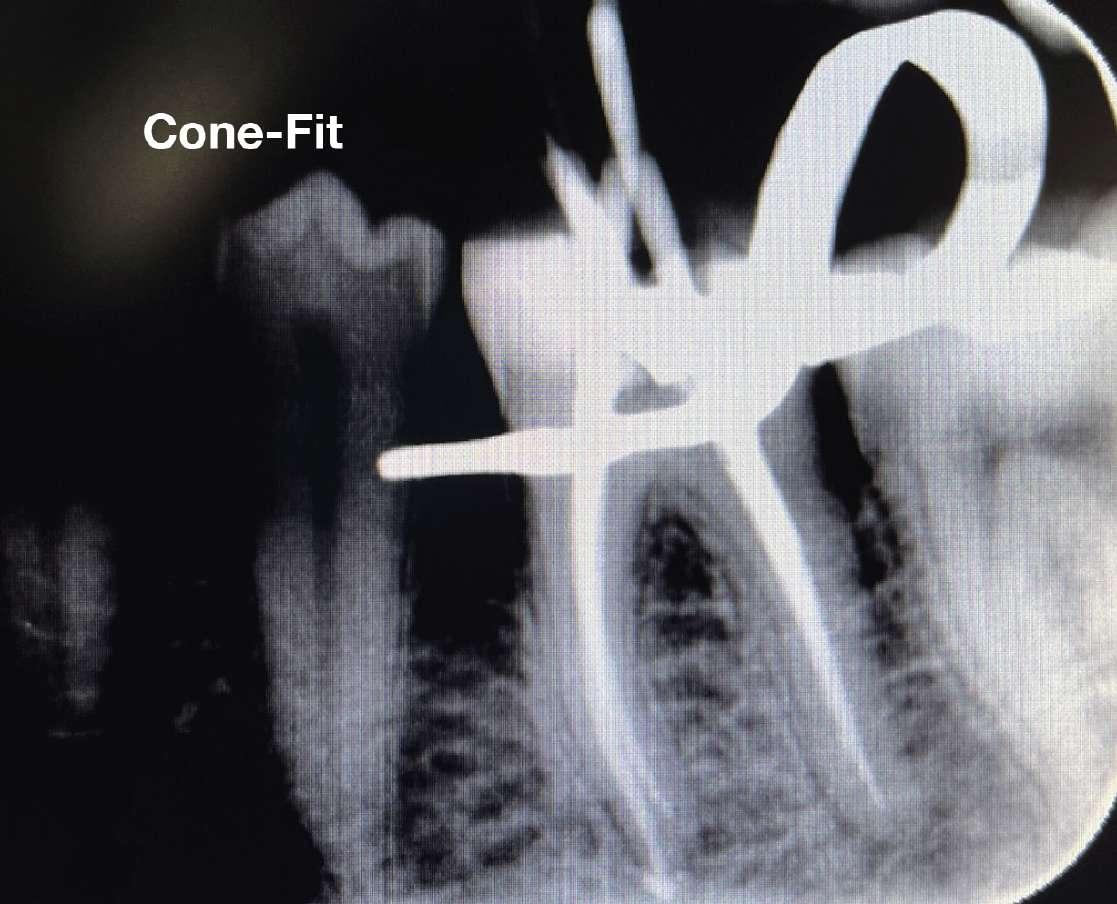

Konuspassung

Die Arbeitslängen wurden mit dem Apex-Locator bestimmt, gefolgt von einer röntgenologischen Bestätigung. Das Kanalsystem wurde mit BUSA BC Sealer und BC GP Point verschlossen. Der Zugang wurde sofort mit einem faserverstärkten Dual-CureKernmaterial wiederhergestellt.

X7s 25.06 bis Widerstand, dann 20.06 bis Widerstand, dann 25.06 bis Widerstand. Arbeitslänge Handfeile bis 15, ggf. 17.04, 30.04, 35.04, 40.04. Für diesen Fall habe ich energisch Handfeilen über meine typische Reihenfolge hinaus bis zu einer #35K verwendet und abschließend mit einer X7 35.04 bei 500 U/min, 2,6 N/ cm Drehmoment gearbeitet.